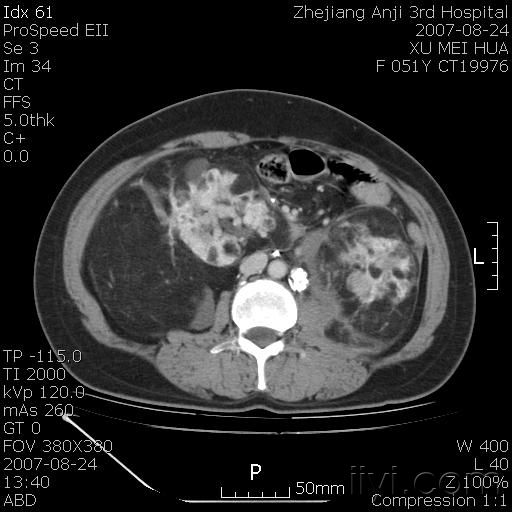

以下是引用还珠格格在2007-8-27 10:19:00的发言:[br]双侧肾脏形态失常,可见巨大的以低密度脂肪为主的混合性肿块,占据中下腹,残留的肾组织轻度强化,增强后肿块内实质部分呈峰窝状强化,低密度区无强化。另左侧肾盂轻度积水。根据病史 考虑 双肾血管平滑肌脂肪瘤可能性大。[br] 鉴别诊断 1、脂肪瘤,境界清楚,肿块内完全是脂肪,几乎没有软组织成分; 2、畸胎瘤:罕见,除有软组织成分外,另一特征是有钙化或骨化影组织。